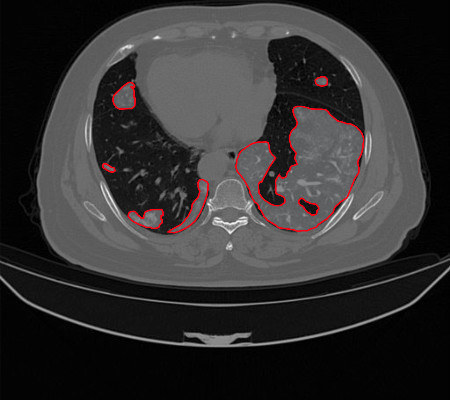

O sistema irá auxiliar os especialistas na triagem/diagnóstico da COVID-19 por meio de imagens de tomografia computadorizada.

O uso da tomografia computadorizada (TC) tem se mostrado uma abordagem promissora para a avaliação de pacientes suspeitos com COVID-19, visto que há uma grande procura para os testes tradicionais. No entanto, é necessário que a tomografia computadorizada seja analisada por um especialista. Pensando nisso, os pesquisadores estão desenvolvendo métodos computacionais que pretendem integrar um software que irá auxiliar os médicos no diagnóstico da Covid-19, como na triagem de pacientes e também promovendo uma segunda opinião.

Os pesquisadores analisaram um conjunto de 708 imagens de tomografia computadorizada, sendo 312 de pessoas com Covid-19 e 396 de pessoas que não possuem a doença. “O método que a gente vem desenvolvendo, consiste na utilização de arquiteturas de inteligência computacional, especificamente as abordagens deep learning (aprendizado profundo). Essas abordagens são técnicas computacionais que analisam as imagens extraindo valores destas. Estes valores, vão fornecer aprendizados ao método desenvolvido, que vai permitir apontar se as imagens da TC têm ou não suspeição de Covid-19", diz o Prof. Dr. Antônio Oseas, do curso de Sistemas de Informação da UFPI, em Picos.